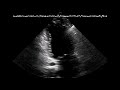

Οι κύστες στις ωοθήκες είναι θύλακες γεμάτοι με υγρό εντός ή επί της επιφανείας μιας ωοθήκης.